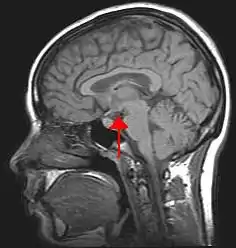

![]() Location of the human hypothalamus | |

The hypothalamus (pl.: hypothalami; from Ancient Greek ὑπό (hupó) 'under', and θάλαμος (thálamos) 'chamber') is a small part of the brain that contains a number of nuclei with a variety of functions. One of the most important functions is to link the nervous system to the endocrine system via the pituitary gland. The hypothalamus is located below the thalamus and is part of the limbic system.[1] It forms the ventral part of the diencephalon. All vertebrate brains contain a hypothalamus.[2] In humans, it is the size of an almond.